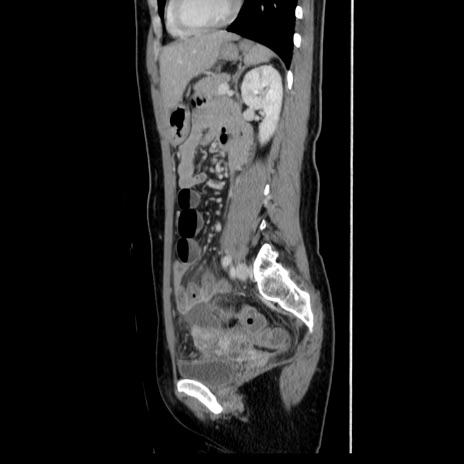

症例39(矢状断像)

【症例】40歳代女性

【主訴】上下腹部痛

【現病歴】2日目から下腹部痛あり。夜間は痛みで眠れなかった。昨日より上腹部痛と下痢が出現。臥位で痛みは軽快したため、休んでいた。本日になって臥位でも立位でも痛みが強くなってきたため救急要請。

【既往歴】子宮内膜症

【身体所見】部:平坦・軟、左上下腹部に圧痛あり、反跳痛あり。

【データ】WBC 21800、CRP 26.78

CT

MRI(4日後)